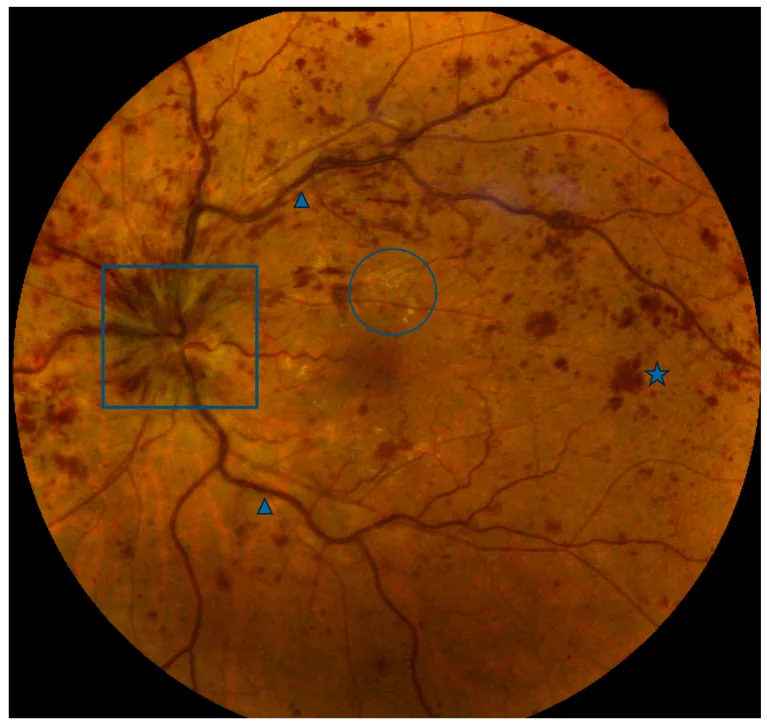

Colcombe J, et al. Retinal Findings and Cardiovascular Risk: Prognostic Conditions, Novel Biomarkers, and Emerging Image Analysis Techniques. J Pers Med. 2023. Figure 1. PM

CI D: PMC10672409. License: CC BY.

眼底全体に多発する網膜 内出血と、静脈の拡張・蛇行がみられる。視神経乳頭 の腫脹や黄斑 周囲の白斑も認め、網膜中心静脈閉塞症の代表的臨床所見を示す画像である。